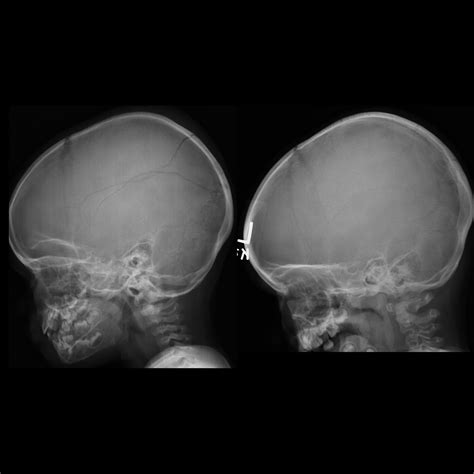

A Baby Skull Xray is a radiographic imaging technique used to visualize the bones of a baby's skull. This non-invasive procedure is essential for diagnosing various conditions, including fractures, deformities, and developmental abnormalities. The X-ray images provide a detailed view of the skull's structure, helping healthcare providers make informed decisions about treatment and care.

Interpreting Baby Skull Xray results requires a trained eye and a deep understanding of pediatric anatomy. Here are some key points to consider:

• Bone Density: The density of the bones can indicate the presence of fractures or other abnormalities.

• Skull Shape: The shape of the skull can provide insights into developmental issues or deformities.

• Fontanelles: The soft spots on a baby’s skull, known as fontanelles, should be checked for proper closure and any signs of swelling or bulging.

• Sutures: The sutures, or the fibrous joints between the skull bones, should be examined for any signs of premature fusion or separation.